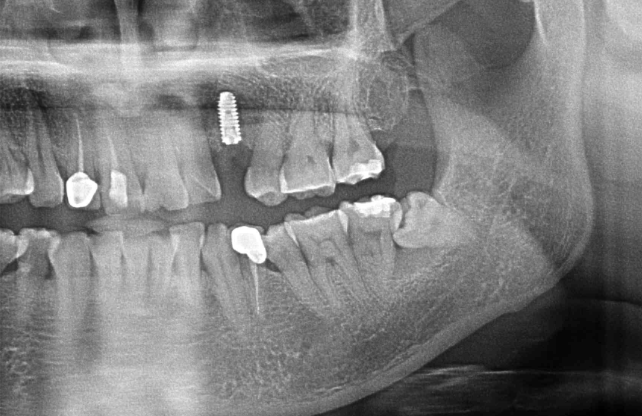

口腔医学技术是国家教育部规定的相关高职高专院校招生专业名称,旨在培育学生专业核心能力——口腔修复工艺技术的基本操作技能。专业核心课程和主要实践环节:口腔解剖生理学、口腔内科、口腔外科、口腔正畸学、口腔修复材料、口腔修复工艺、口腔医学、口腔美学、口腔修复工艺实训、口腔科见习、毕业实习等,以及各校主要特色课程和实践环节。目标是培养掌握口腔医学的基本理论和口腔治疗技术与工艺技术的基本操作技能,从事牙齿整复和整形技术工作的高级技术应用性专门人才。